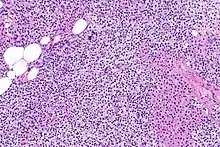

Parathyroid glands are normally composed of chief cells, adipocytes and scattered oxyphil cells.[27][14] Chief cells are thought to be responsible for the production, storage and secretion of parathyroid hormone. These cells appear light and dark with a prominent Golgi body and endoplasmic reticulum. In electron micrographs, secretory vesicles can be seen in and around the Golgi and at the cell membrane. These cells also contain prominent cytoplasmic adipose.[27][14] Upon onset of hyperplasia these cells are described as having a nodular pattern with enlargement of protein synthesis machinery such as the endoplasmic reticulum and Golgi. Increased secretory vesicles are seen and decreased intercellular fat is characteristic.[27][24] Oxyphil cells also appear hyperplasic however, these cells are much less prominent.

Biochemically, there are changes in function between normal and nodular hyperplastic parathyroid glands. These changes involve proto-oncogene expression and activation of proliferative pathways while inactivating apoptotic pathways.[28] In nodular parathyroid tissue increased expression of TGF-a, a growth factor, and EGFR, its receptor, results in aggressive proliferation and further downregulation of vitamin D receptors, which act to suppress hormone secretions.[25][8][28] Furthermore, the proliferative marker, Ki67 is seen to be highly expressed in the secondary nodular hyperplastic state.[28][25] Tumour suppressor genes have also been highlighted as being silenced or degraded in nodular hyperplastic parathyroid tissue.[8][28] One such gene, p53, has been shown to regulate multiple tumour suppressor pathways and in tumorigenesis can be degraded by b-catenin. This pathway, in some aspect, is mediated by CACYBP, which is highly expressed in nodular parathyroid hyperplasia.[28]